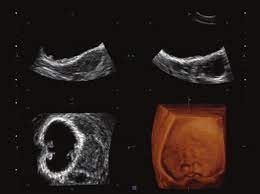

Toshiba Xario™ XG je barevný ultrazvukový systém se sdílenými službami Doppler, který kombinuje vynikající kvalitu obrazu s ergonomickým designem. Tento všestranný přístroj je vybaven řadou pokročilých funkcí, které zajišťují konzistentní poskytování vysoce kvalitních snímků v širokém spektru klinických aplikací, včetně břicha, prsou, malých částí, štítné žlázy a specializovaných OB/GYN aplikací s 3D/4D zobrazením.

- 3D/4D možnosti: Pokročilé zobrazení pro OB/GYN aplikace.